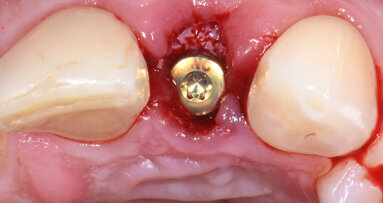

La paziente è stata sottoposta a profilassi antibiotica tramite somministrazione di 2 g di amoxicillina/acido clavulanico (Augmentin, GlaxoSmithKline) un’ora prima della chirurgia. La paziente inoltre ha eseguito sciacqui orali con clorexidina 0,2% (Corsodyl, GlaxoSmithKline) per due minuti e assunto 100 mg di nimesulide (Aulin, Roche). Il trattamento post-operatorio è proseguito con l’assunzione di 1 g di amoxicillina/acido clavulanico ogni 12 ore per 6 giorni e nimesulide 100 mg ogni 12 ore per 3 giorni, oltre alla continuazione degli sciacqui orali con clorexidina 0,2% per 10 giorni. L’anestesia locale è stata eseguita mediante infiltrazione di articaina all’1% ed epinefrina 1:100.000 (Molteni Dental). Dopo aver aperto due lembi gengivali tra le posizioni 21–23 e 11–13, gli impianti sono stati posizionati attraverso l’impiego della dima chirurgica. Gli impianti sono stati inseriti ottimizzandone l’ingombro vestibolo-palatale, in relazione al ridotto spessore crestale (Fig. 4). L’intervento si è concluso eseguendo una sutura a punti semplici staccati con utilizzo di filo riassorbibile Vycril Rapid 5-0 (Johnson & Johnson).

Fig. 4_Procedimento chirurgico finalizzato all’inserimento degli impianti B1ONE HIGH in posizione 22 (2,7 x 12 mm) e 12 (3,2 x 12 mm) mediante chirurgia guidata. Al termine dell’inserimento, è visibile la connessione intracoronale dell’impianto monopezzo.